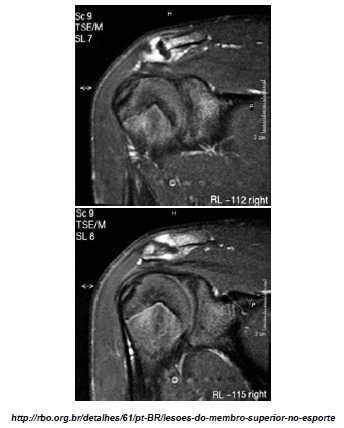

Observe a imagem de ressonância magnética, abaixo:

O achado evidente na imagem, após análise, é: